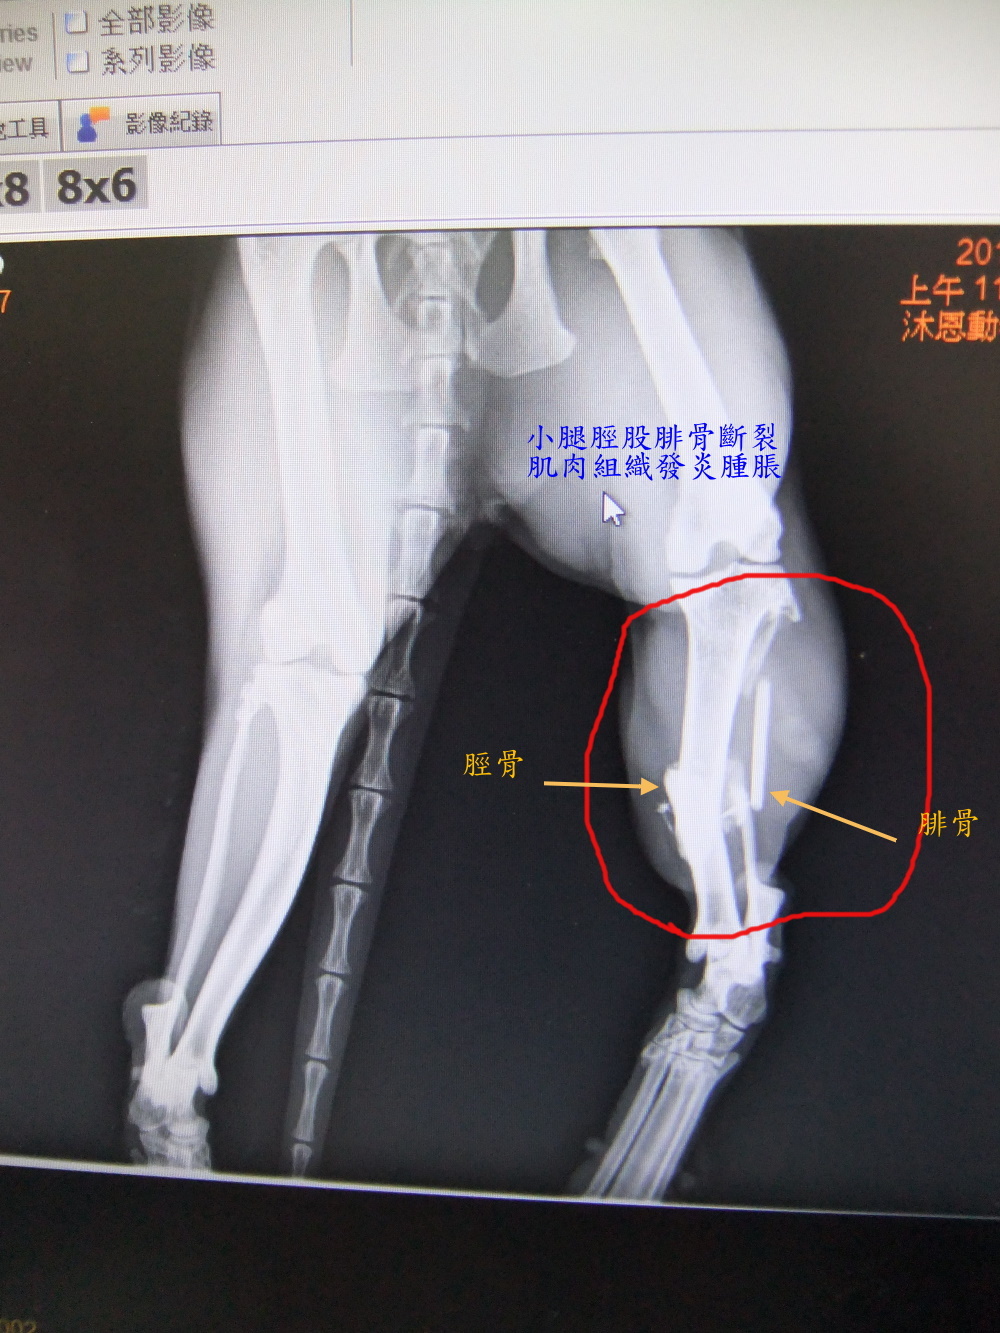

主題: 有家歸不得的乳牛骨折貓--脛骨腓骨斷裂修復手術 申請者姓名: 王惠貞 花色: 申請日期: 2012-04-27 01:20:58 申請者部落格: 申請者臉書網址: 所在縣市/合作醫院: 台北市/其他院所醫助專案(醫院請先MAIL溝通) 治療費用: 15000元 需求人數: 15人 已結案 (2012-06-21 01:13:31) 報名人員: Chi-Ju Chen(已付款)、吳家儀(已付款)、sally(已付款)、sally(已付款)、sally(已付款)、Emilia Chen(已付款)、Ku-ai Gina Chen(已付款)、philip(已付款)、GiMi Li(已付款)、波波(已付款)、張珍妮(已付款)、Hsin-Yi Chiao(已付款)、Shih Ju Chiu(已付款)、Irena(已付款)、Ny To(已付款)、 候補人員: 小舟、小舟、小舟、 動物病情說明: 這隻tnr乳牛貓生活的很坎坷,被「人」盯上,有「里」歸不得,被下令不准待在出生至長大的里,以換取其他貓咪的生活權,一年多來安置不同的志工家,逃跑了兩次,這次逃跑後沒這麼幸運,牠在連棟各大樓鐵皮屋頂上活動兩個月之久,志工頂樓隔間有放飼料及水,但4月中,在消失3天後周六晚被找到,虛脫的倒在巷子旁,經協會幫助,緊急先送最近的動物醫院,醫生驗血報告所有指數都很高,嚴重脫水,左小腿研判骨折,可能從高處掉落有三天之久沒進食喝水,先住院打點滴期盼指數恢復正常,由於醫院沒x光機、開刀台,週一轉至沐恩動物醫院治療,x光片顯示左小腿脛骨腓骨斷裂,右腿骨板根部關節處傷口深,有發炎,部分血指數有下降但肝腎指數仍高,醫生週四才能開刀打骨鈑,所以先作了骨架並住院觀察,目前術後傷口恢復不錯但食慾極差,為省醫療費自行帶回照顧,希望他能打起精神恢復以前愛吃愛叫的個性,並繼續和我們一起尋找能夠自由與幸福並存的地方,住院及開刀醫療費用兩家醫院2870+27855=30725,費用對我們來說負擔高,需15000元幫助,希望大家一起幫忙,一人1000元!剩餘醫療費及後續取出骨鈑費用我們自行負擔,以節省資金可救助其他之貓咪